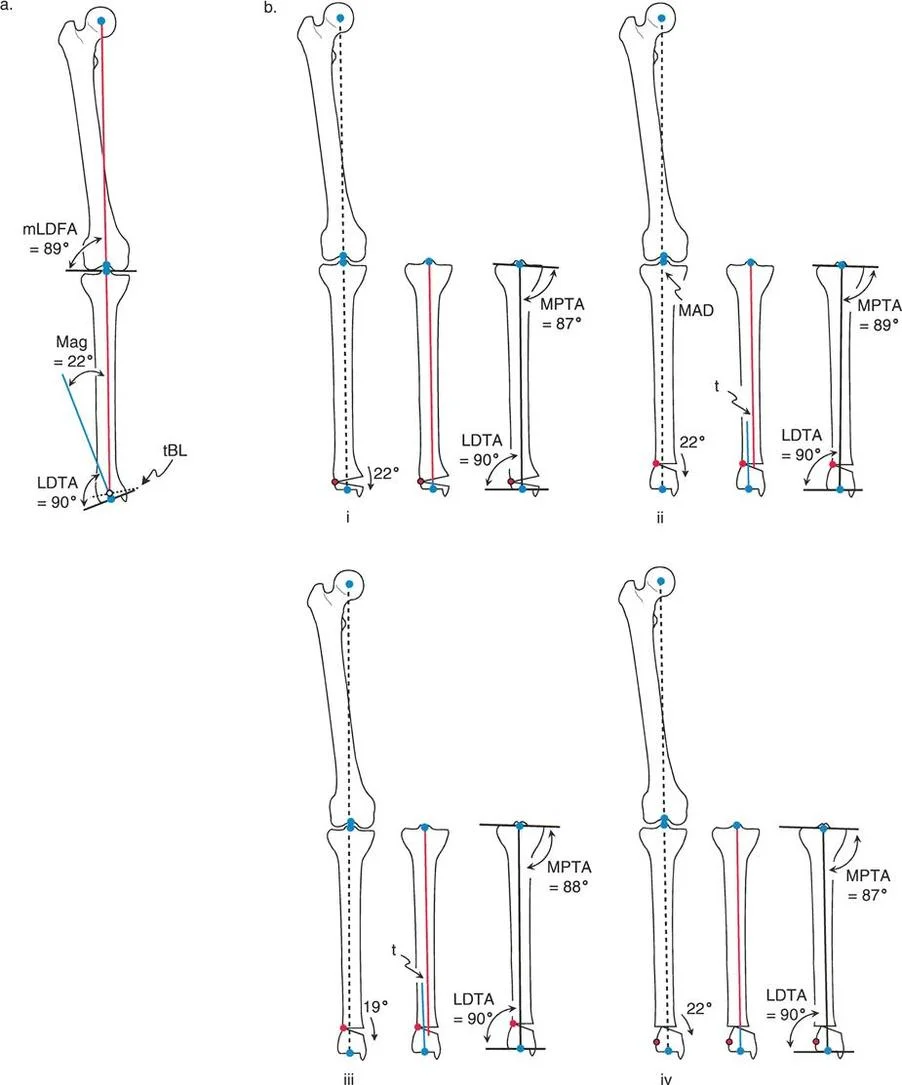

هذا الدليل الشامل يستعرض الاعتبارات الحاسمة لتطبيق الأجهزة، وتحديد مواضع المفاصل الاصطناعية (المفصلات)، وآليات الشد، والتسلسل الاستراتيجي للتصحيحات التدريجية. سواء كان الجراح يستخدم مثبتات إليزاروف الدائرية التقليدية، أو أنظمة الهيكسابود الحديثة (مثل جهاز تايلور الفراغي Taylor Spatial Frame)، أو المثبتات أحادية الجانب، فإن القواعد الهندسية التي تحكم مركز دوران الانحراف (CORA)، ومحور تصحيح الانحراف (ACA)، وانحراف المحور الميكانيكي (MAD) تظل مطلقة ولا تقبل الخطأ.

من خلال إتقان هذه المبادئ، يمكن لجراحي العظام، وعلى رأسهم الأستاذ الدكتور محمد هطيف في صنعاء، التلاعب بقطع العظام في الفراغ ثلاثي الأبعاد بشكل موثوق، مما يضمن التوجيه الأمثل للمفاصل - مستهدفين بشكل خاص الزاوية الفخذية الأنسية البعيدة الطبيعية (mLDFA) والزاوية الظنبوبية القريبة الأنسية (MPTA) - مع احترام البيولوجيا الدقيقة للعظم المتكون حديثًا.

تؤثر هذه التشوهات على زوايا المفاصل مثل الزاوية الفخذية الأنسية البعيدة (mLDFA) والزاوية الظنبوبية القريبة الأنسية (MPTA)، والتي يجب أن تكون ضمن نطاقات طبيعية لضمان وظيفة المفصل المثلى. تصحيح هذه الزوايا بدقة هو جوهر العلاج.

القياسات الهندسية:

- باستخدام صور الأشعة السينية الطويلة، يقوم الأستاذ الدكتور محمد هطيف بإجراء قياسات هندسية دقيقة لتحديد الزوايا غير الطبيعية (مثل mLDFA و MPTA)، ومقدار القصر، ودرجة الدوران، وأي انحرافات في المحور الميكانيكي. هذه القياسات هي الأساس لتخطيط الجراحة بدقة متناهية.

فهم قواعد بالي لقطع العظم أمر لا غنى عنه لتخطيط الإطار:

- قاعدة قطع العظم 1: عندما يمر قطع العظم ومحور تصحيح الانحراف (ACA) كلاهما عبر مركز دوران الانحراف (CORA)، فإن نهايات العظم ستنحرف دون ترجمة (انزياح). يتم استعادة المحور الميكانيكي، وتظل نهايات العظم متقاربة تمامًا، مما يخلق تصحيحًا كلاسيكيًا "إسفينيًا مفتوحًا" أو "إسفينيًا مغلقًا".

- قاعدة قطع العظم 2: عندما يمر محور تصحيح الانحراف (ACA) عبر مركز دوران الانحراف (CORA)، ولكن يتم إجراء قطع العظم على مستوى مختلف (غالبًا بسبب ضعف جودة العظم عند CORA أو مشاكل في الجلد)، فإن نهايات العظم ستنحرف وتخضع لترجمة محسوبة ومقصودة لإعادة محاذاة المحور الميكانيكي.

- قاعدة قطع العظم 3: (للاكمال) عندما يمر قطع العظم عبر مركز دوران الانحراف (CORA)، ولكن يتم وضع محور تصحيح الانحراف (ACA) خارج CORA، سيتم إنشاء تشوه ترجمة جديد، وهو خطأ شائع في وضع المفصلات غير المخطط له جيدًا.